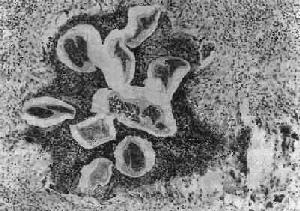

图19-16 丝虫性淋巴管炎

图中可见数个切断的死虫体,周围有嗜酸性脓肿及肉芽肿反应

(1)淋巴管炎:多发生在较大的淋巴管,以下肢、精索、附睾、腹腔内淋巴管及乳腺等处较多见。肉眼观,急性期发炎的淋巴管呈一条红线样自上而下蔓延,形成所谓离心性淋巴管炎。当皮肤表浅微细淋巴管亦被波及时,局部皮肤则呈弥漫性红肿,称为丹毒性皮炎。镜下,常见淋巴管扩张、内皮细胞肿胀增生,管壁水肿增厚和嗜酸性粒细胞及单核细胞浸润。虫体死亡后对组织刺激强烈,引起凝固性坏死及大量嗜酸性粒细胞浸润,形成所谓嗜酸性脓肿。坏死组织中央可见死亡虫体断片及脱出在虫体外的微丝蚴,病变附近可找到Charcot-Leyden结晶。慢性期在脓肿周围出现类上皮细胞、巨噬细胞及异物巨细胞或Langhans巨细胞,形成结核样肉芽肿(图19-16)。随着虫体的钙化,肉芽肿逐渐纤维化,形成同心圆状排列的实心纤维索,使管腔完全闭塞,形成闭塞性淋巴管炎,而引起一系列继发改变。